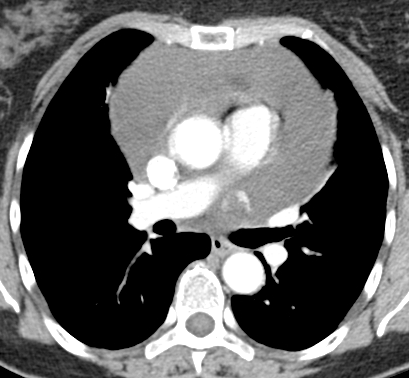

In view of the absent primary lesions elsewhere and enlarged lymph nodes in the pericardial fat pad pericardial mesothelioma was the probable diagnosis. Pattern of spread initially to adjacent pleura. Ct is most commonly used for imaging assessment of mesothelioma and sufficient for accurate staging of disease in most patients.

The role of computed tomography scanning in the initial assessment and the follow up of malignant pleural mesothelioma. Malignant pericardial mesothelioma is characterized by unrepresentative solid growth of the mesothelium with a structure of atypical cavities environed by fibrous stroma. Therapeutic and diagnostic pericardial and pleural tapping was done and sent for cytological examination which showed presence of malignant cells in the pericardial aspirate and absence of the same in the pleural aspirate.

However ct and mr imaging are particularly useful as sensitive and noninvasive methods for evaluating loculated or hemorrhagic pericardial effusion constrictive pericarditis and pericardial masses. Pleural mass or nodular thickening of soft tissue attenuation. Although pmpm is infrequent it is the third most common tumor around the heartpericardium after angiosarcoma 33 and rhabdomyosarcoma 20.